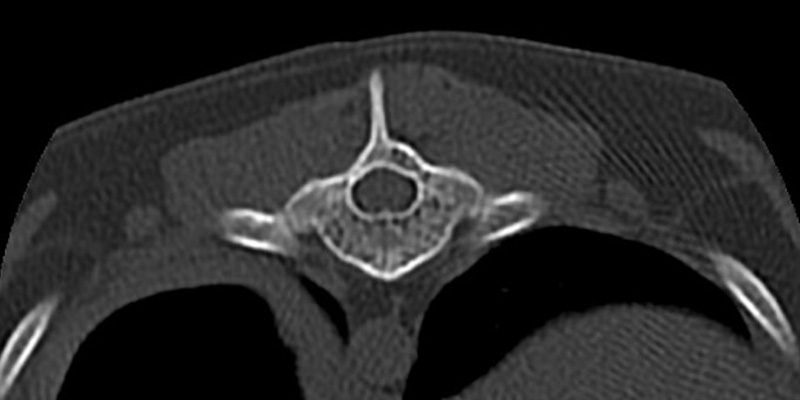

One of Max’s vertebra (axial view) not experiencing spinal cord compression: normal